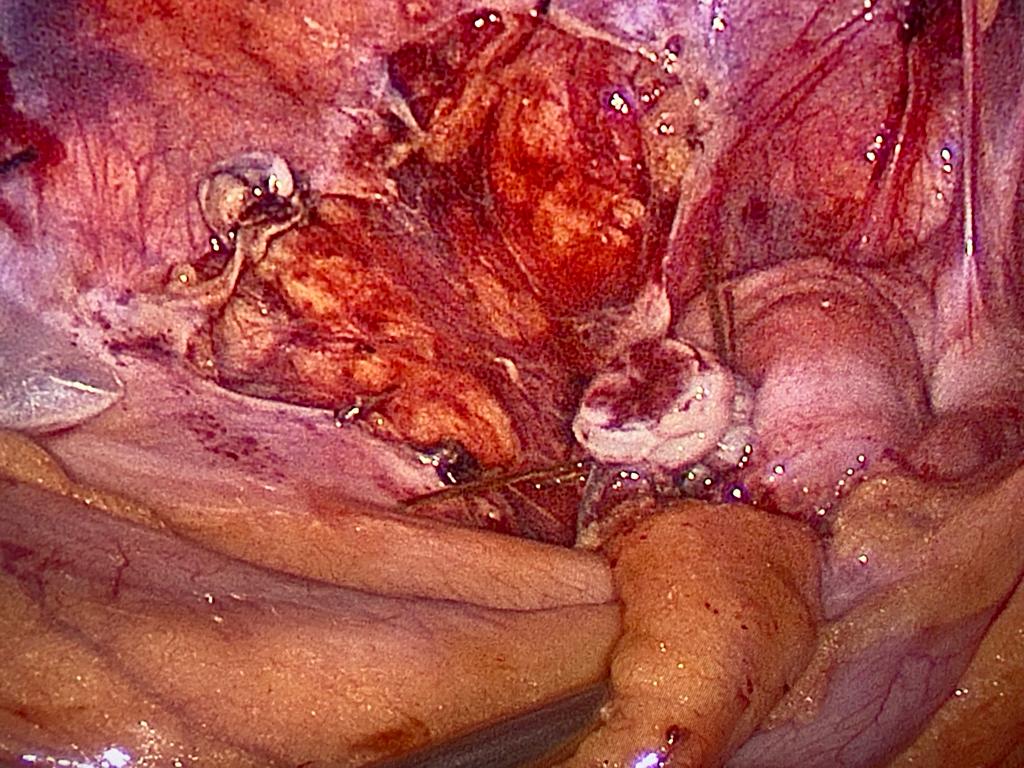

Big posterior fibroid uterus with anterior fibroid and big ovarian cyst. Total laparoscopic hysterectomy done ( TLH )

Bulky uterus with big posterior fibroid. Completely done Laparoscopically ( TLH)